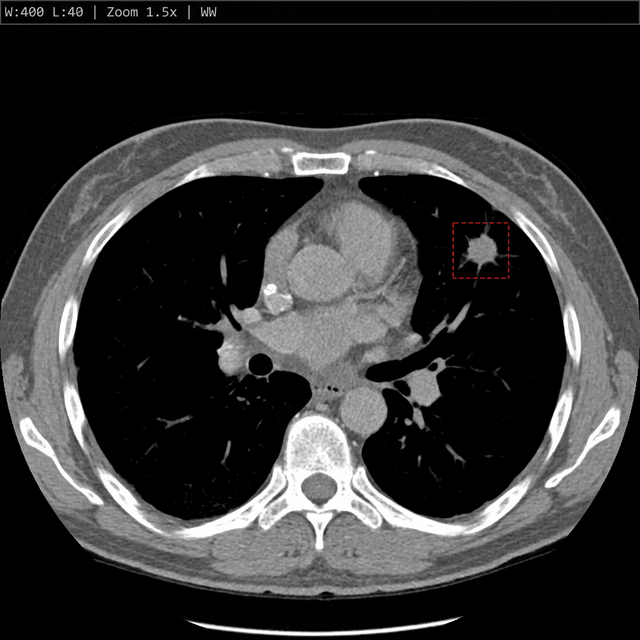

AI annotations, bounding boxes, and measurements are baked directly into the DICOM — rendered as Secondary Captures readable in any viewer. Clinical history and labs are pre-populated into your dictation software.